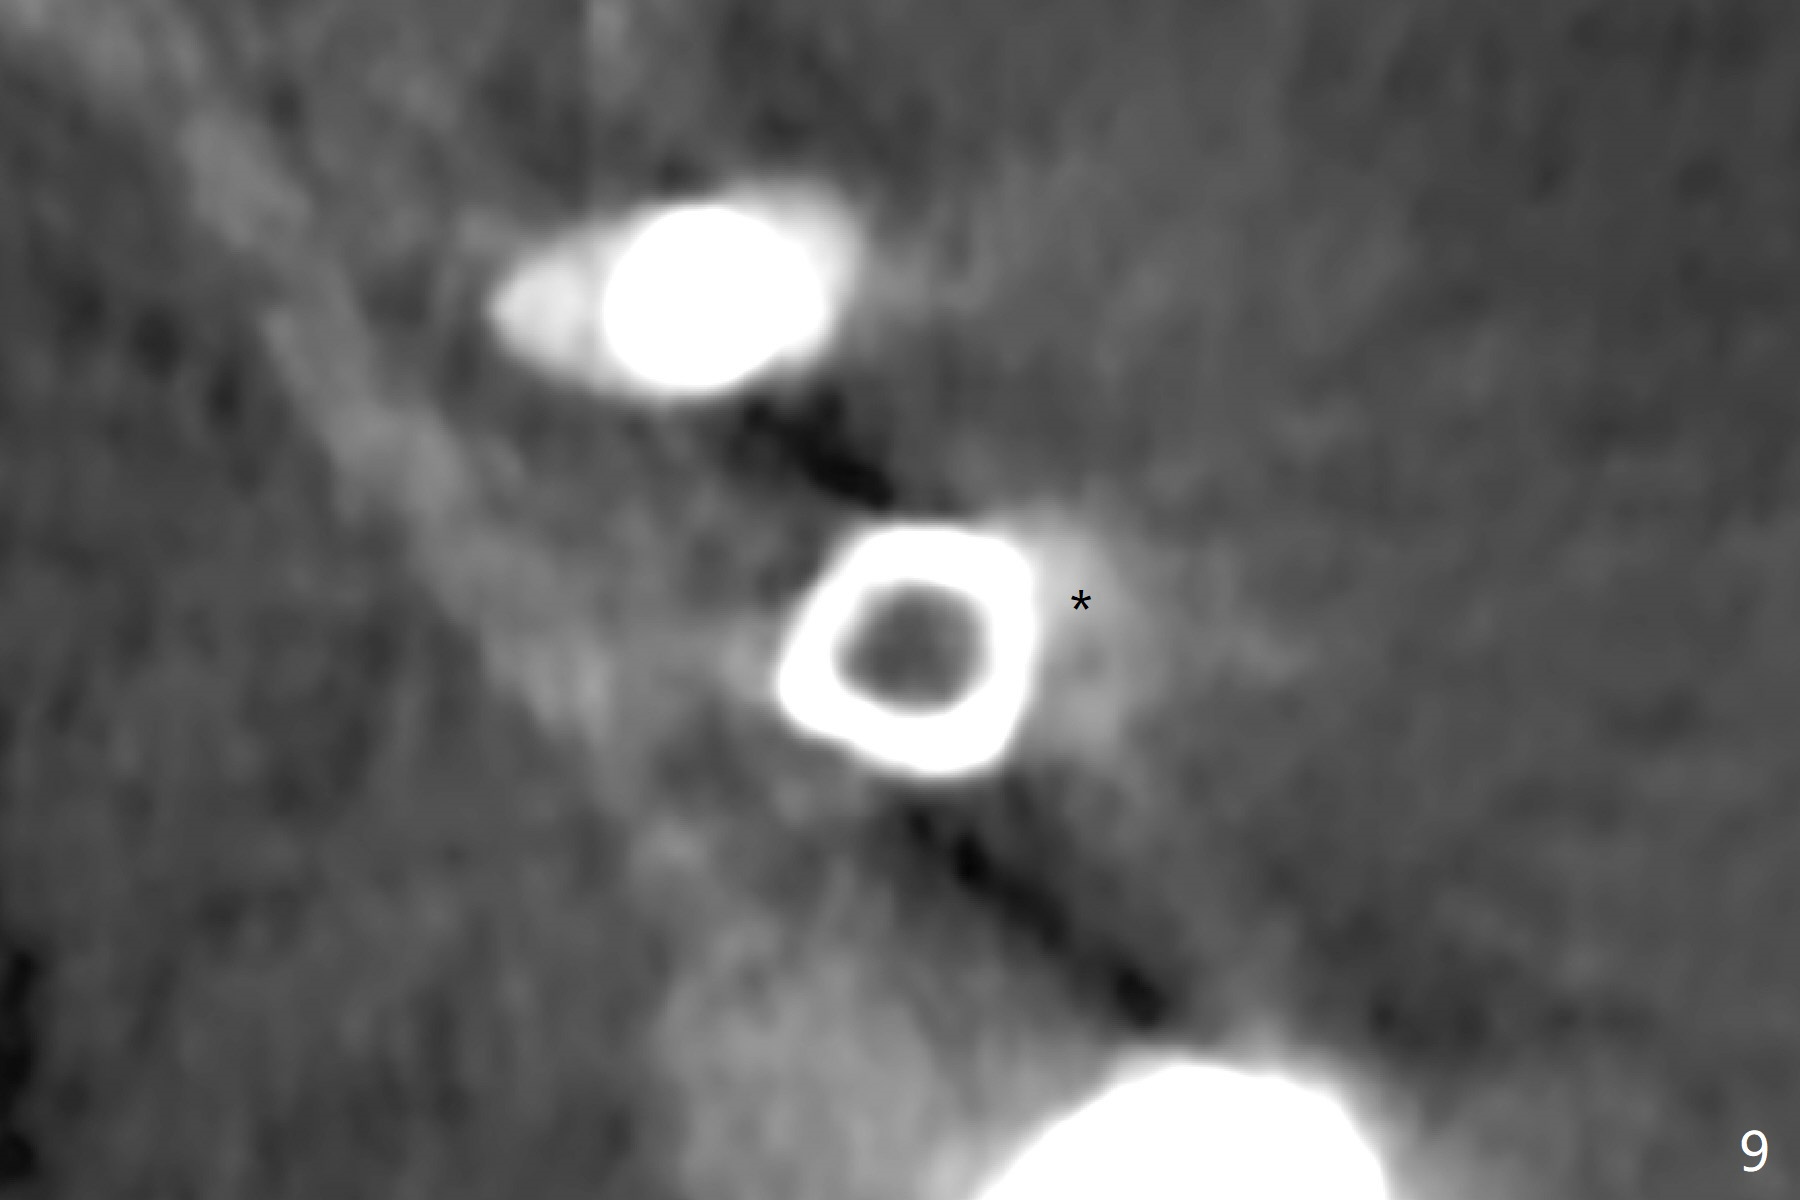

After osteotomy with guide and 2.2 mm drill for ~ 4 mm at #14, a bone expander (1.3/2.3 mm) is used free hand for sinus lift for 12 mm (from the gingival margin, Fig.1; a 10 mm long implant is planned). Following the next expander (1.7/3.1 mm) for the same depth with binding, the sinus membrane is suspected to have perforated. A piece of Osteogen Plug is inserted into the osteotomy as deep as possible with the purpose to repair the sinus membrane (no bone graft being used), followed by placing a 3.5x8.5 (instead of 10) mm implant with insertion torque ~ 25 Ncm (Fig.2,7-9, CT). As compared to preop CT (Fig.4-6), the previously grafted bone is lifted into the sinus by the bone expanders and the implant (Fig.7*). At the same time, the grafted bone has been condensed and pushed buccally (B) (Fig.8,9 *). A 4x6 mm healing abutment is inserted (Fig.3). There is crestal bone loss 6 months postop (Fig.10). Buccal plate atrophy involves the 3 implants in a row (Fig.11). The crown is loose 1 year 8 m post cementation (Fig.12). After proximal reduction, the crown/abutment rotates and sits down substantially (Fig.13). Since the crown is extremely long, it cannot be seated together with the abutment. The latter is seated with X-ray confirmation before proximal reduction of the crown (Fig.14).